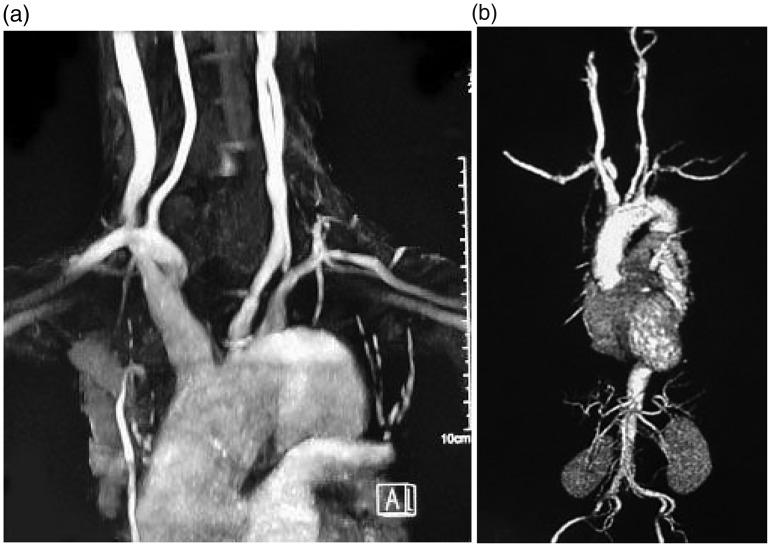

We herein report a case involving a 56-year-old man who had experienced neck and lower back pain since the age of 23 years. Ankylosing spondylitis (AS) was diagnosed at 41 years of age, and treatment with sulfasalazine was initiated. At 44 years of age, the patient developed respiratory distress on exertion and chest pain. Aortic regurgitation (AR) was diagnosed via echocardiography, and the patient presented to our hospital for close examination and treatment. Coronary computed tomography angiography revealed no lesions in the coronary artery; however, magnetic resonance angiography revealed stenotic lesions in the left common carotid artery and left subclavian artery. Based on the findings of a physical examination, fundus examination, and blood tests, the patient was diagnosed with AS with concurrent Takayasu arteritis (TA). Upon administration of steroids to alleviate inflammation caused by an autoimmune mechanism, the patient's chest symptoms and inflammatory findings improved. AR was treated with aortic valve replacement and prosthetic blood vessel replacement, after which the patient progressed well. Intraoperative aortic biopsy revealed findings pathologically consistent with TA. Although AS with concurrent AR is well described, AS with concurrent TA, as in the present case, is rare.

我们在此报告一例病例,患者为一名56岁男性,自23岁起就一直遭受颈部和下背部疼痛。41岁时被诊断为强直性脊柱炎(AS),并开始使用柳氮磺胺吡啶进行治疗。44岁时,患者在运动时出现呼吸窘迫和胸痛。经超声心动图诊断为主动脉瓣关闭不全(AR),随后患者前来我院进行进一步检查和治疗。冠状动脉计算机断层扫描血管造影显示冠状动脉无病变;然而,磁共振血管造影显示左颈总动脉和左锁骨下动脉有狭窄病变。根据体格检查、眼底检查和血液检查结果,该患者被诊断为AS并发高安动脉炎(TA)。在给予类固醇以减轻自身免疫机制引起的炎症后,患者的胸部症状和炎症表现有所改善。AR通过主动脉瓣置换和人工血管置换进行治疗,此后患者恢复良好。术中主动脉活检显示病理结果与TA一致。虽然AS并发AR已有充分描述,但如本病例中AS并发TA的情况则较为罕见。